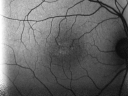

60-year-old man has juxtafoveal retinal telangiectasis in both eyes with vision change. Recently his vision has been declining. He had more trouble reading. I last saw him in March of 2010. Since then he notices he is not as good as he was.

VISUAL ACUITY: OD 20/50, OS 20/70. IOP: OD 11, OS 12. The posterior chamber intraocular lens is in good position in both eyes.

OD: Vertical C/D ratio is 0.3. There is no posterior vitreous separation. There are patchy telangiectatic vessels and retinal crystals.

OS: Vertical C/D ratio is 0.5. There is no posterior vitreous separation. There is hemorrhage in the macula with pigment epithelium thickening superonasal to the fovea.

FLUORESCEIN ANGIOGRAPHY: Fluorescein angiography shows bright hyperfluorescence more in the macula in the left eye than the right eye.

1. JUXTAFOVEAL RETINAL TELANGIECTASIS – BOTH EYES

2. STAGE FIVE – LEFT EYE

3. WET AGE-RELATED MACULAR DEGENERATION – LEFT EYE

DISCUSSION: I explained to the patient with Avastin there is a chance of drying the macula in the left eye and improving the vision. I treated the left eye with intravitreal injection of Avastin (1.25 mg/0.05 ml) without any difficulty today.